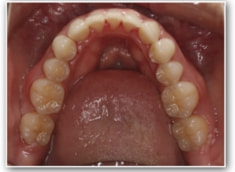

治療後